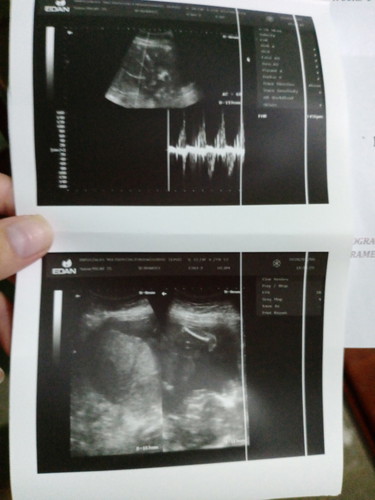

Nag paultrasound po ako. 20 weeks and 4 days po ako. sabi girl daw po ang baby ko. base po sa mga nababasa ko may chance pa daw na magbago yun kasi masyado pang maaga. totoo po ba yun? Thank you po sa sasagot

5 mos. onwards po accurate na makita ang gender ni baby. Not unless si baby medyo natatakpan nya ung private part nya un po me chance na mag iba dahil hindi clear. Pero kung kitang kita naman po ang private part ni baby, sure na po yan